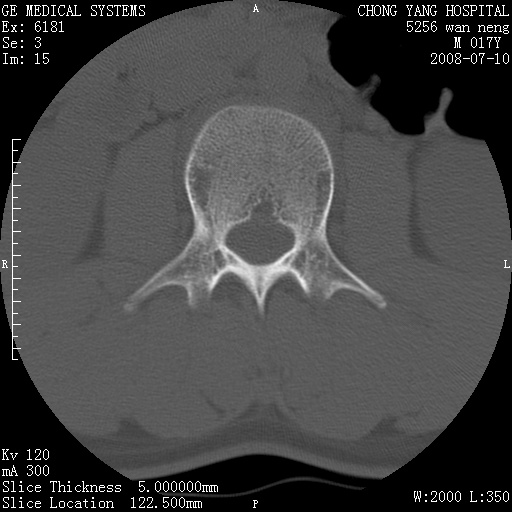

腰3、4椎弓崩裂

腰3、4椎弓不连

支持:腰3、4椎弓峡部崩裂。

腰3、4椎弓峡部不连

支持:腰3、4椎弓峡部崩解。

腰3、4,如受过外伤则为陈旧骨折,否则为骨质不连

图片漂亮,目前也只能看到腰3、4骨质不连

腰3、4椎弓峡部裂。

腰3、4椎弓峡部裂。支持

重建图像见多个椎弓峡部不连(不足为据),平扫未见异常。

支持腰3、4椎弓峡部崩裂。